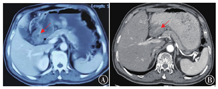

2020年10月13日因活动后胸闷气短就诊我院心内科,完善血常规提示血红蛋白76 g/L(为小细胞低色素性贫血)。胸部CT:双肺炎性病变伴间质性病变。颅脑MRI、放射性核素骨扫描、浅表淋巴结超声检查未见肿瘤转移性病变。2020年10月18日行程序性死亡蛋白配体-1(programmed death-ligand 1,PD-L1)检测:肿瘤细胞阳性比例分数(tumor proportion score,TPS)2%~3%,综合阳性评分(combined positive score,CPS)4。2020年10月22日基因检测提示:人体表皮生长因子受体-2(human epidermal growth factor receptor-2,HER-2)扩增阴性;高肿瘤突变负荷(tumor mutation burden-high,TMB-H);MSI-H。期间规律复查血红蛋白,血红蛋白进行性下降,2020年10月29日血红蛋白59 g/L。为进一步诊治转入肿瘤内科,查体:美国东部肿瘤协作组(ECOG)评分3~4分,神志清,精神差,重度贫血貌,卧床状态,浅表淋巴结未触及肿大,双肺呼吸音清晰,未闻及干湿性啰音;心律齐,未闻及病理性杂音;腹软,剑突下轻压痛,无反跳痛及肌紧张,肝脾未触及,腹部未触及包块,移动性浊音阴性,双下肢轻度凹陷性水肿。给予输注红细胞改善贫血及一般情况,病情好转后自2020年11月5日起给予替雷利珠单抗(200 mg/次,静脉滴注,1次/d,第1天,21 d为1周期,1年后改为每个月1周期)治疗。5个周期后评估疗效为部分缓解(partial response,PR)(见图1B),胃镜:胃窦溃疡并幽门梗阻。胃窦活检病理结果:黏膜慢性炎伴急性炎,纤维肉芽组织增生,溃疡形成,建议治疗后复查。治疗7、14、16个周期后评估疗效为维持PR。2021年11月15日于我院行PET-CT(见图2):胃腺癌治疗后,胃窦处胃壁明显增厚(胃窦胃壁最厚处27 mm),局部葡萄糖代谢增高(SUVmax3.9),考虑治疗后肿瘤组织仍有活性。自替雷利珠单抗治疗第1周期后患者血红蛋白均维持在90 g/L以上,肿瘤标志物进行性下降并维持在正常水平,治疗期间暂未发现药物相关不良反应,患者依从性良好。末次随访为2022年6月4日,患者精神、进食、睡眠尚可,大小便正常,无不适症状。